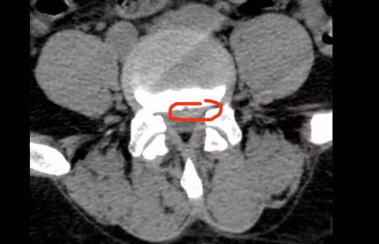

图中标红部分为突出的椎间盘

“与传统‘开大刀’手术相比,UBE属于脊柱微创手术,该手术对椎旁肌肉损伤较小,能够较大程度地保留完整的脊柱结构,维持术后脊柱的稳定。术后第一天患者就可以下地行走,避免了传统术后需要卧床两周以上甚至1个月以上的情况。”李东风医生详细地把单侧双通道内镜技术的优势和手术方式李师傅做了说明。